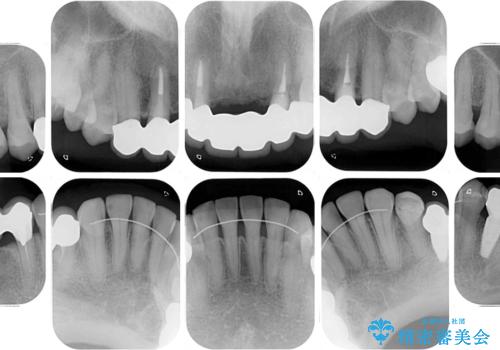

- 口の中に気になるところが沢山あるものの、地元ではなかなか治療を行ってくれるところがないとのことで、沖縄県の離島より来院された患者様です。

金属を使用した前歯のブリッジや奥歯の銀歯は全てオールセラミッククラウンまたはセラミックインレーとし、左下の奥歯はインプラントにより治療を行うこととしました。

外科処置を行うため、治癒を待つ期間が数ヶ月あるため、その期間を利用して下顎前歯のスペースを矯正治療で閉じることとしました。

遠方からの来院であったので、1回の治療時間を長めにし、できる限りの処置を集中して行うことで、来院回数を減らすことができました。

矯正治療までは考えていなかったそうですが、物が挟まっていた前歯のスペースがなくなり、矯正治療を行って良かったとのことでした。

初診カウンセリングを含めて13回の通院で治療を終えることができ、患者様には大変満足していただきました。